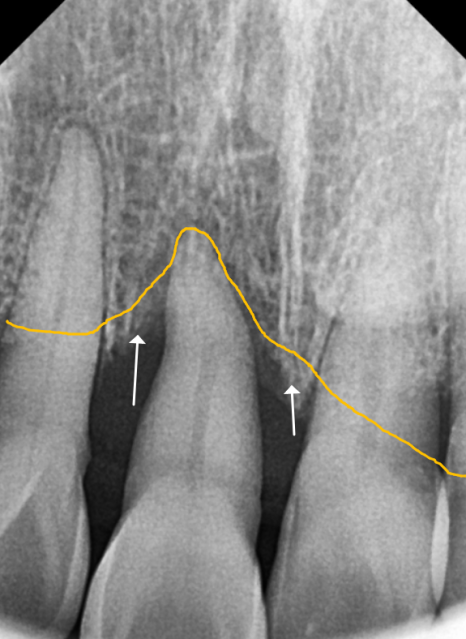

방사선 사진을 살펴볼게요~

매끈해보여야 할 치아 뿌리 쪽에

돌기처럼 무언가 붙어있는게 보이시나요?

251201

바로 치석인데요.

사실 치석은 밀도가 낮아

방사선 사진상에는

잘 나타나지 않는 경우가 많아요.

그런데 만약 엑스레이 사진에서

이처럼 치아 옆면이 매끄럽지 않고

돌기처럼 튀어나온 것이 보인다면,

정상적인 잇몸 상태 , 치아 뿌리 면이 매끄러움

치은연하치석이 뿌리면에 돌기처럼 붙어있는 모습

그건 치석이 이미 엄청나게

두껍고 단단하게 쌓였다는 뜻이에요..ㅜㅜ